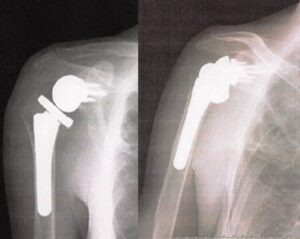

術後画像

術直後Xp